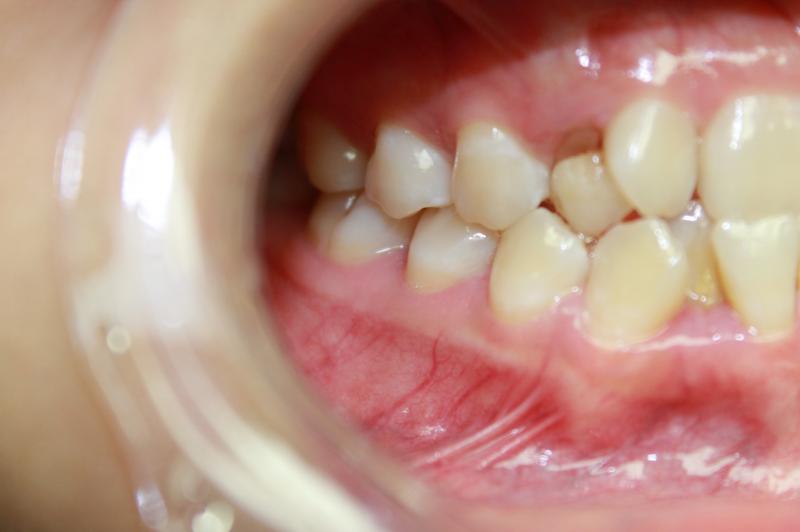

INVISALIGN - 13 months, 1 lower tooth removal, 1 series of aligners to align teeth and create the proper amount of space for 2 cantilever bridge to replace congenitally missing cuspids. COSMETIC DENTISTRY - 2 porcelain cantilever bridges and cosmetic bonding to reshape incisors and close gingival spaces. TOTAL TREATMENT TIME, 15 months

Cosmetic Dentistry, Mid-line Asymetry, Missing Teeth, Severe Crowding